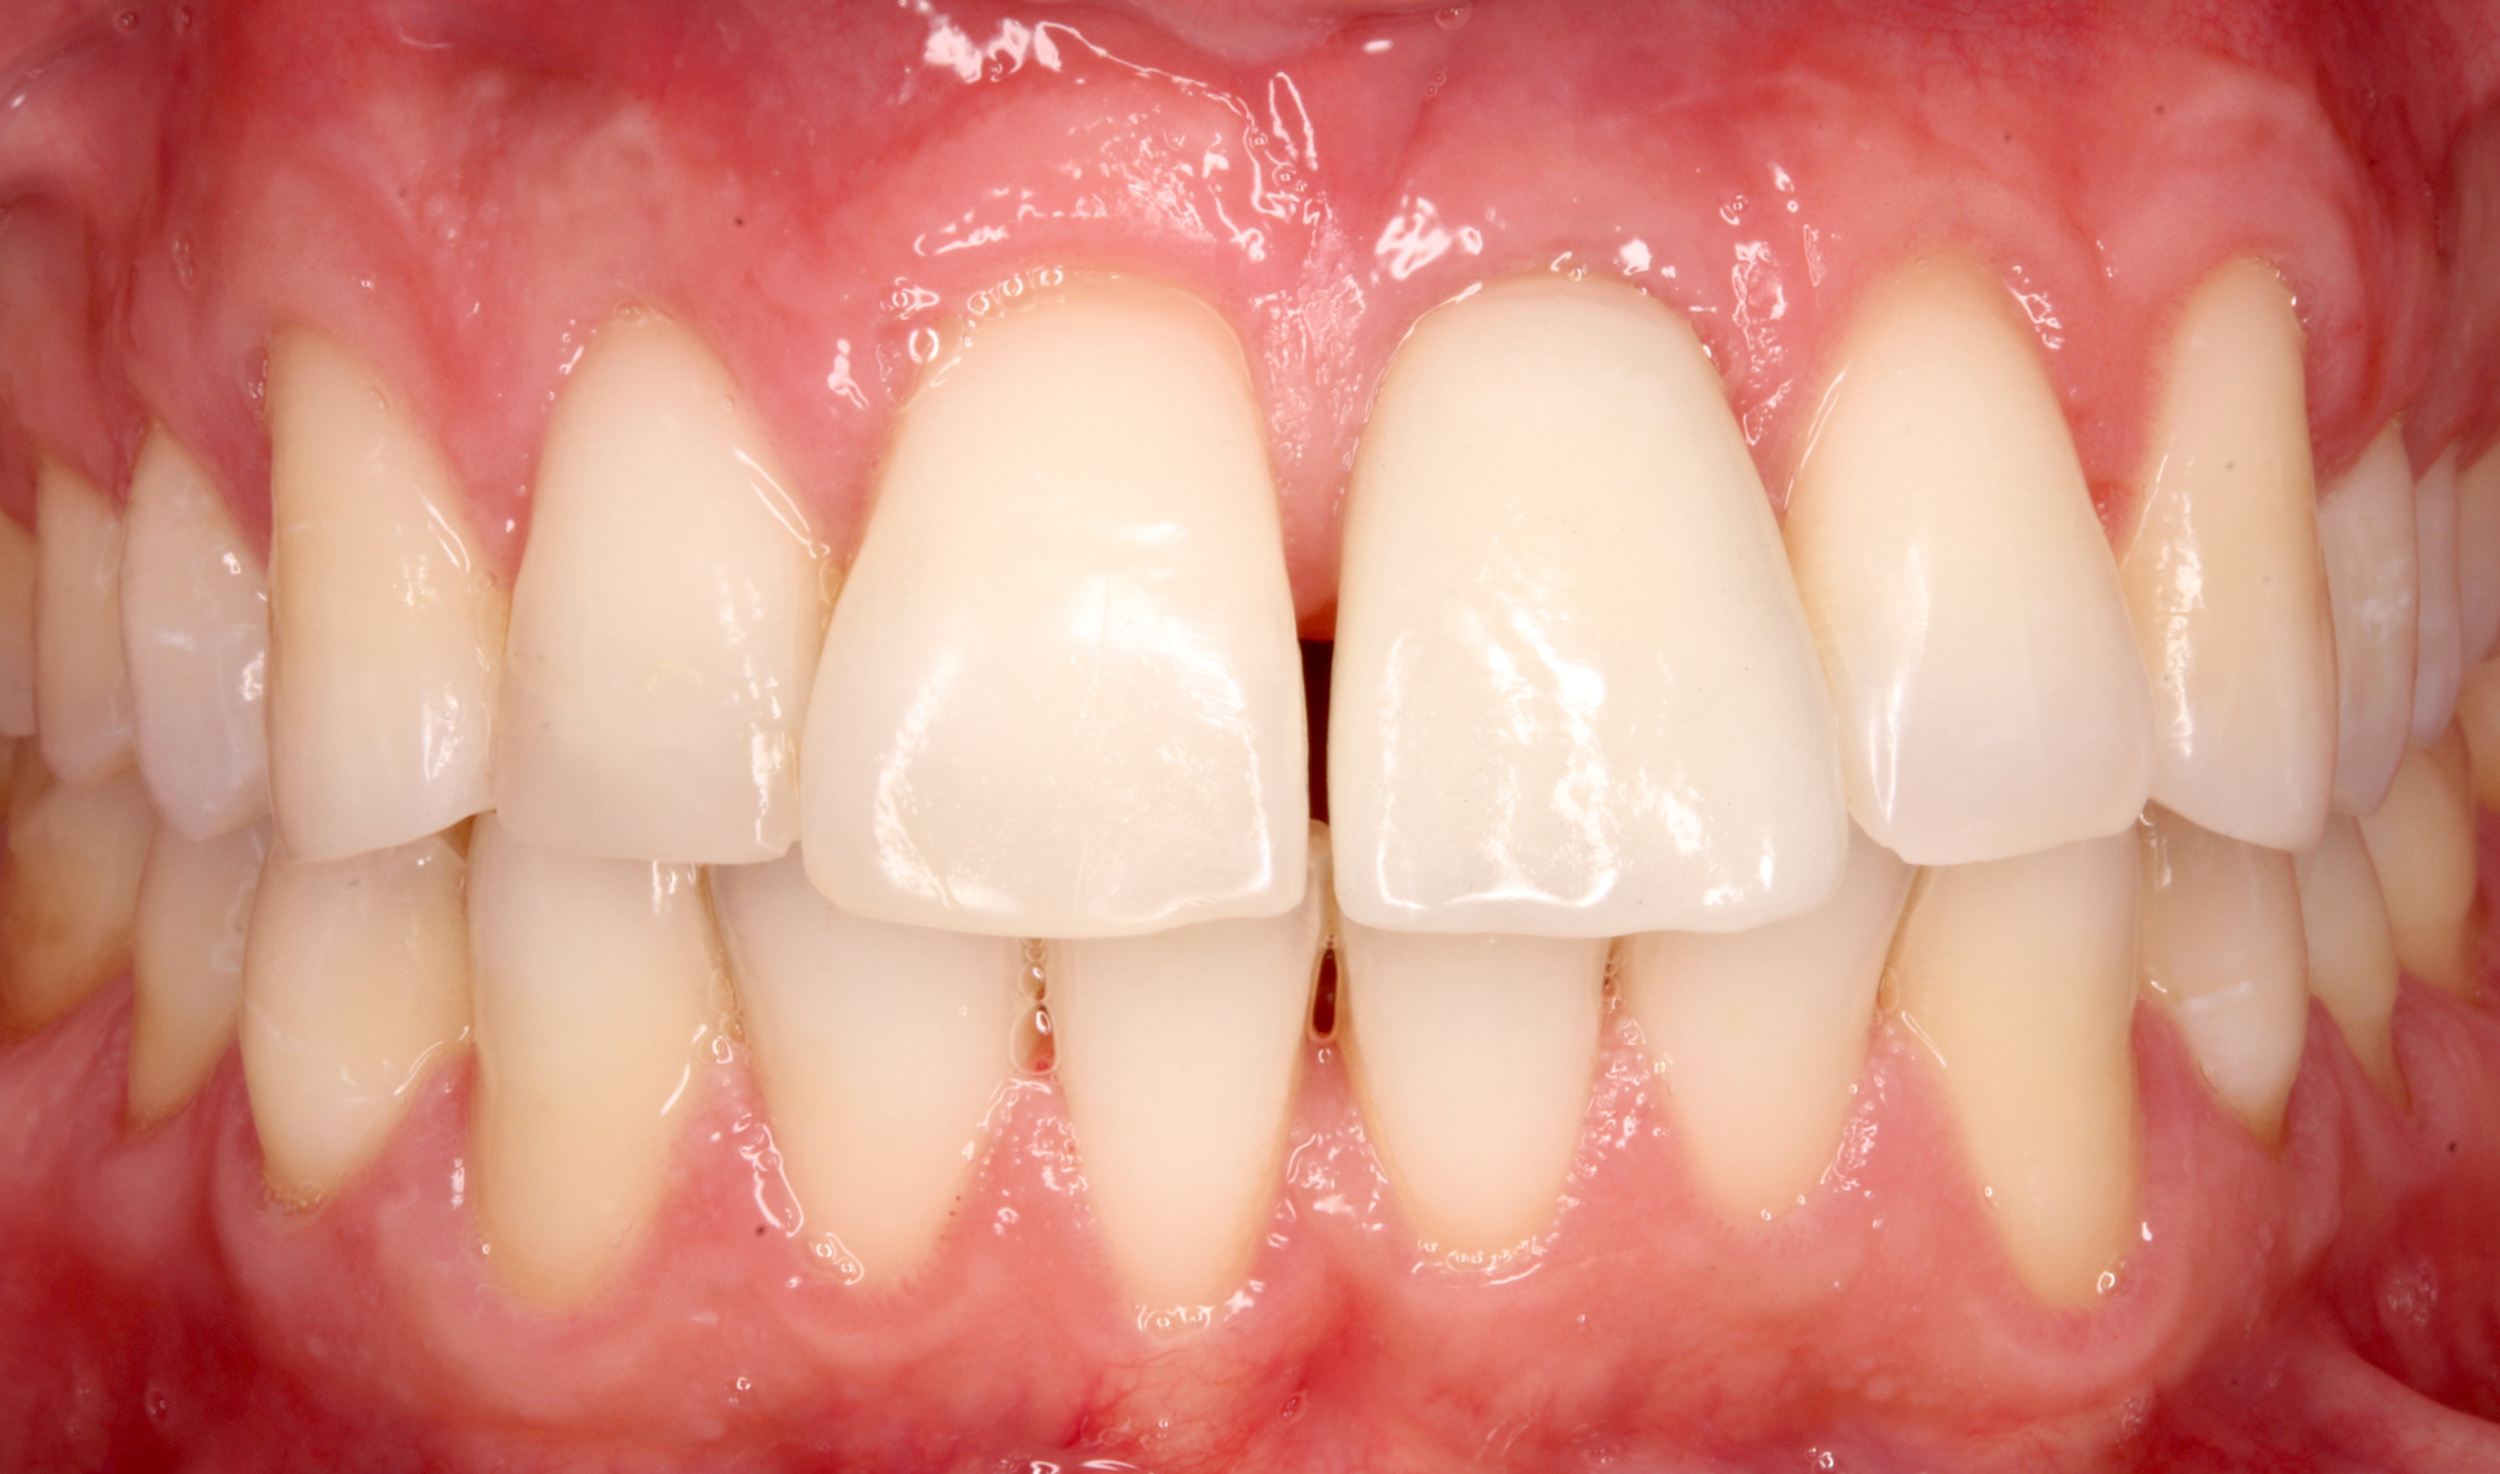

Riabilitazioni complesse con mantenimento

dei denti naturali

In alcune situazioni, anche quando è necessario inserire più impianti, è possibile preservare i denti naturali presenti e valorizzarli con altri trattamenti come ortodonzia, faccette, corone o innesti gengivali. Questo approccio permette di combinare diverse tecniche per ottenere un risultato finale armonioso, funzionale e naturale, rispettando al massimo la struttura dentaria residua.

Caso 3 - Caso 4

PRIMA

DOPO